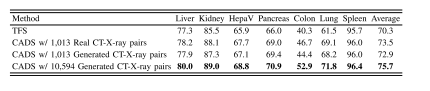

ABLE IXPERFORMANCE OF TFS, CADS USING 1,013 REAL OR GENERATEDCT-X-RAY PAIRS FROM THE COVID19-CT DATASET, AND CADSUSING 10,594 GENERATED CT-X-RAY PAIRS FROM THEDEEPLESION DATASET.THE BEST RESULT IN EACHCOLUMN IS HIGHLIGHTED WITH BOLD

表9 TFS模型、使用COVID19-CT数据集1013组真实或生成CT-X射线配对数据的CADS模型,以及使用DeepLesion数据集10594组生成CT-X射线配对数据的CADS模型的性能对比。每列中的最佳结果以粗体突出显示 (说明:原标题“ABLE IX”应为“TABLE IX”的拼写误差,已按学术表格编号规范修正为“表9”;明确区分了不同CADS模型所用的数据集来源、数据类型及数据量,清晰体现实验变量差异,符合学术表格标题的信息完整性要求。)